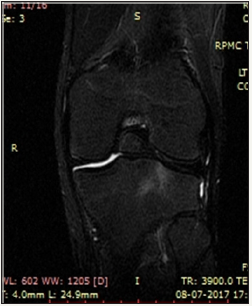

Figure 1: multiple intra-articular ossicles in coronal T1W.

We present a case of 14 year old male child who had history of pain in the right knee while climbing upstairs for long duration. There was no history of any significant trauma in the past. After clinical examination by the orthopaedician in the outpatient department patient came to our department for MRI right knee with strong clinical suspicion of ACL injury. We did MRI of right of the patient and found a large ossicle intra-articularly which was impinging the ACL. The ossicle showed the signal intensity of bone on all pulse sequences. No other pathology was noted in the right knee joint (Figure 1-5).